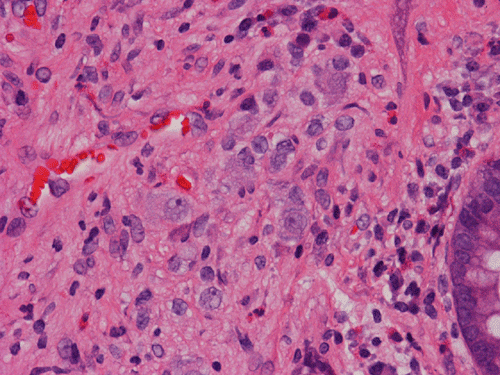

Clinical information The patient was a 54 year-old man. On screening colonoscopy, a small nodular polyp was found. The following are representative images from this polyp.

Pathology of the Case: The lesion is a small polypoid nodule of mucosa. At scanning magnification, there seems to be a mucosal flattening with erosion. There is focal reduction of glands and increased spacing in between glands (Panel A). Mucin production by the glandular epithelium is normal and there is no inflammatory cell infiltration (Panel B). There is no epithelial proliferation. On the other hand, the glands seems to be separated by spindle cells reminiscent of peripheral nerve(Panel B). On high magnification, there are some large neuronal or ganglionic appearing cell clusters in the lamina propria (Panel C). These neural tissue and ganglionic cells are positive for S100 protein (Panel D and E).

DIAGNOSIS: Solitary ganglioneuroma of colon.

Gastrointestinal GN is uncommon and has been found in the stomach, duodenum, ileum, appendix and large intestine. Polypoid GNs are usually small, sessile or pedunculated polyps. These lesions are solitary or few in number and most of them are located in the large intestine. Histologically, neural tissue may occur as patchy distributions of ganglionic and neural parenchymal tissue in the lamina or nodular, neurofibromatosis like pattern in the mucosa and submucosa. A mixed pattern can occur. As expected, the neural component can be well demonstrated by immunohistochemistry for S100 protein and the ganglionic cells can be well demonstrated by immunohistochemistry for neurofilament proteins.